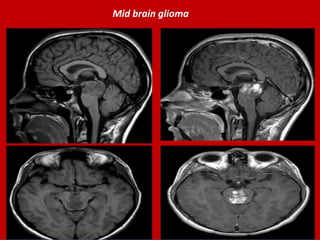

Mid brain glioma